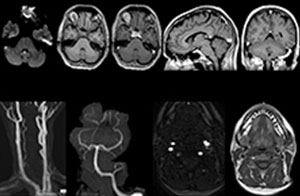

To minimize the time taken to perform scans, rapid MRI examination protocols (ExamCards) were developed, shortening the total scanning time to even less than 10 minutes in some exams. Techniques like mDIXON (modified DIXON) are used for robust capturing of fat-free MRI images in a hectic ED environment.

A range of protocol sheets was developed to help ensure that referring physicians order the most appropriate MRI exam. The optimized MRI protocols also include 3D contrast-enhanced imaging, allowing neurosurgeons to comfortably use the isotropic data in the operating room while performing stereotaxic surgery.

For Dr. Karis, the next goals for the neuro ED include converting the exams for acute stroke and TIA patients from CT to MRI, offering an alternative management option for these patients. Also, collaboration between other departments is currently underway, encouraging the performance of targeted exams with the ED MRI. These improvements in workflow and faster turnaround times may result in further reductions in scanning time.